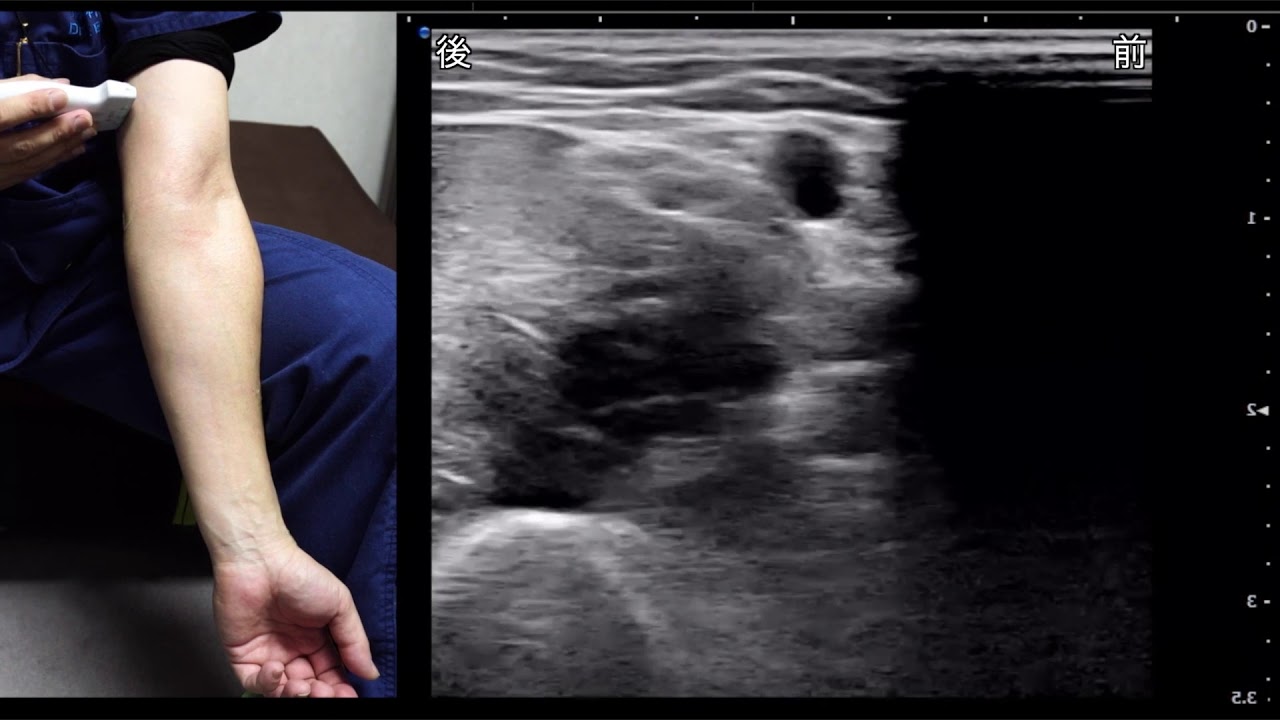

採血点滴 これを見れば注意点がわかる!腕の神経走行

採血点滴の神経損傷しないためのコツ

しっかりと解剖を理解して穿刺を行いましょう.

起こってしまうときは少確率でもありますが,そうならないように確率を低くすることは大事です